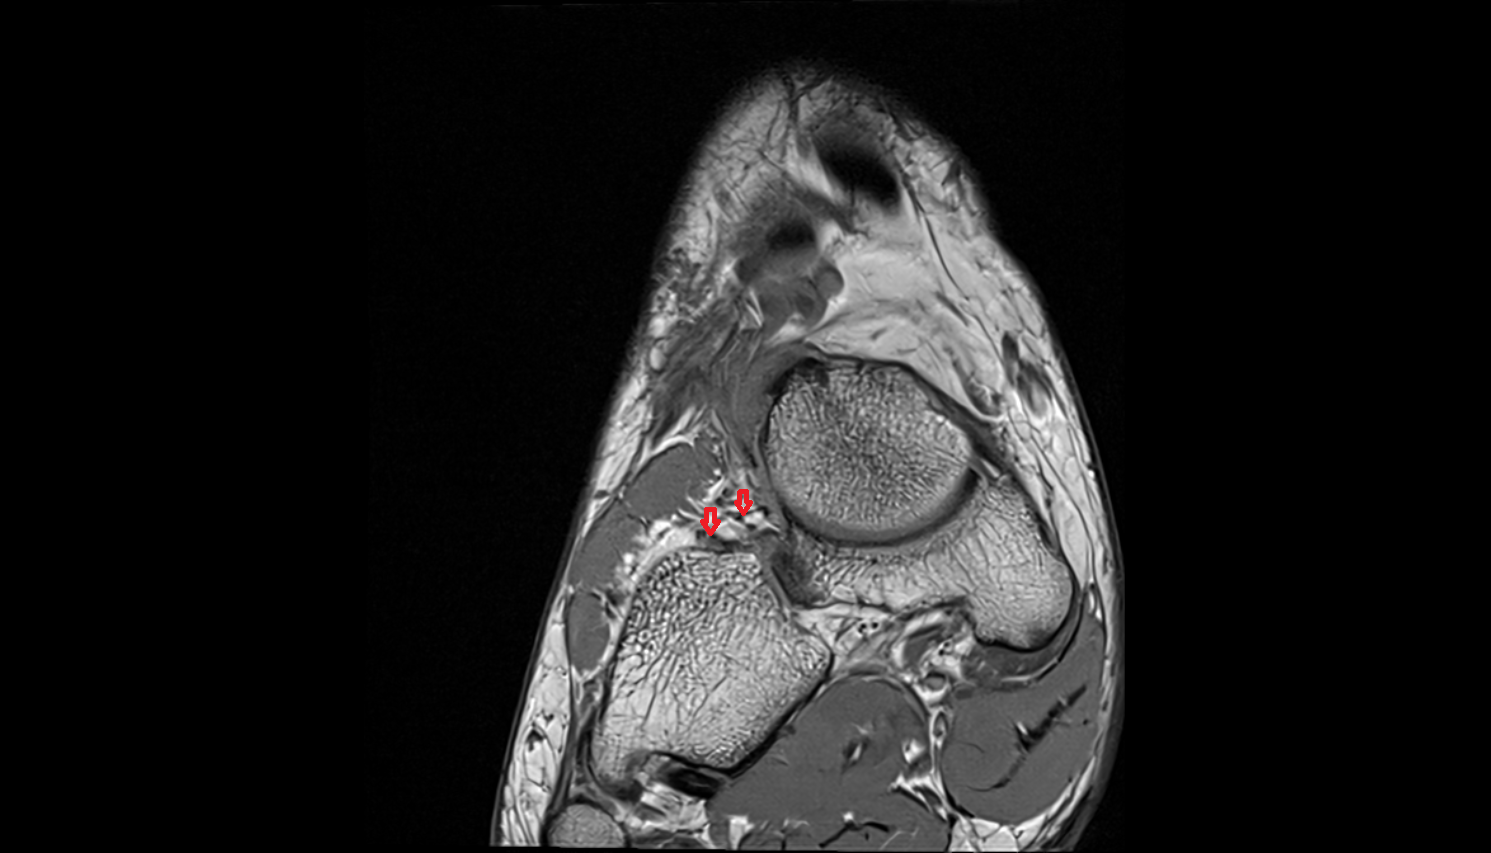

- Temporomandibular joint

- Mandibular condyle

- Mandibular fossa